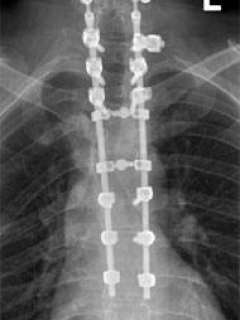

I made the decision that he would need to undergo extensive surgery, simultaneously treating the fractures in his neck and mid-back. I had a long talk with his wife regarding the procedure. We used computer image guidance, a cutting edge technology in which placement of the bone screws were guided by a computer workstation. He required two surgeries, and a total of sixteen titanium screws and two rods were placed (Fig. 2). His spine was fused from the C5-T8 levels.